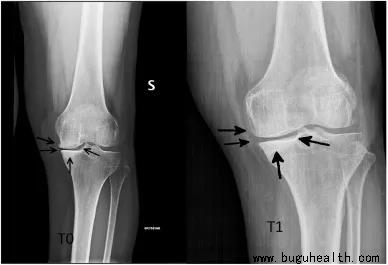

为此,意大利比萨大学的 Andrea Malorgio 在《运动医学与健康科学(英文)》(SMHS)中发表了一项个案研究,以探讨其联系。作者招募了一名 72 岁的患有 KOA 的女性,为其进行康复训练和医学检查。2016年11月的第一次 RX 拍片显示内侧关节应力大,并伴有半月板疼痛和骨的改变(图1)。

图1 左图像基线RX,2016年11月;右图像对照RX,2018年8月

研究结果显示,高强度杠铃举训练能使KOA患者关节形态重塑优化,功能性负荷分布增大,关节间隙变窄(JSN)速度下降甚至逆转,骨质疏松减少,不适症状改善及生活质量提高,WOMAC骨关节炎指数下降了34%,最终得分为9%。